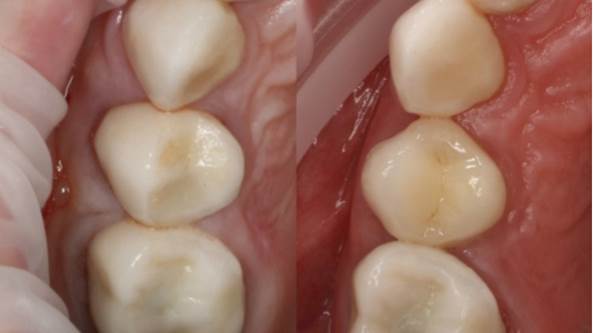

“AnyRidge & R2GATE show stable results

after immediate extraction, immediate implant placement, & immediate loading,

even with low bone density.”